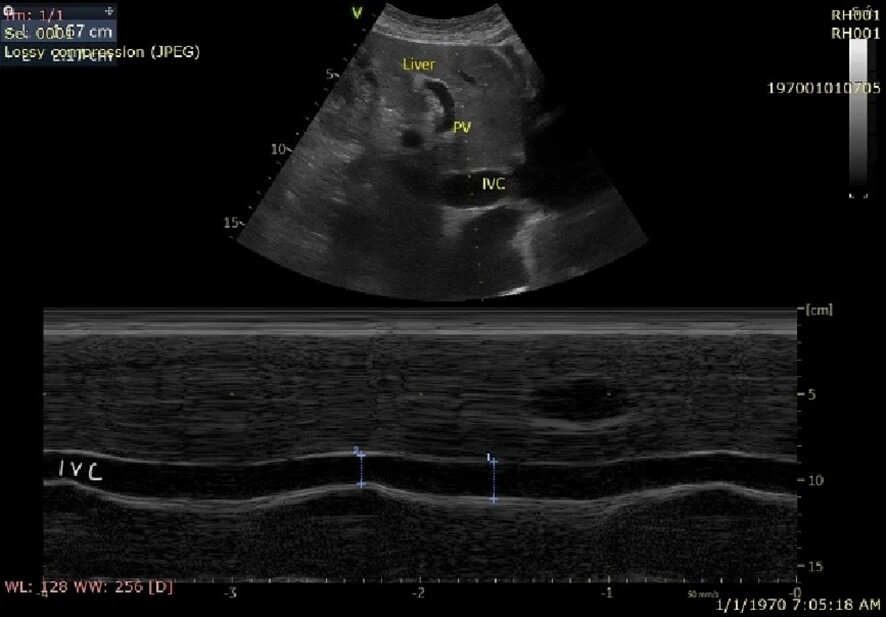

Чтобы оценить изменение диаметра нижней полой вены (НПВ) в течение дыхательного цикла, мы используем индекс коллапса НПВ (IVC collapsibility index, IVCCI). Врач измеряет максимальный (IVCmax) и минимальный (IVCmin) диаметры НПВ на протяжении цикла. IVCCI рассчитывается по формуле (IVCmax - IVCmin) / IVCmax. У пациентов на спонтанном дыхании диаметр НПВ менее 2,1 см с IVCCI более 50% (на вдохе при дыхании через нос) обычно указывает на центральное венозное давление (ЦВД) 0-5 см.вод.ст. Диаметр НПВ менее 2,1 см с IVCCI более 50% (на вдохе при дыхании через нос) обычно указывает на повышенное давление в правом предсердии 10-20 см.вод.ст. IVCCI не валидирован для пациентов на искусственной вентиляции легких с положительным давлением.

Рис. 2. Датчик в проекции эпигастрия. Демонстрируется нижняя полая вена (IVC) и ее респираторная вариабельность, а также воротная вена (PV)